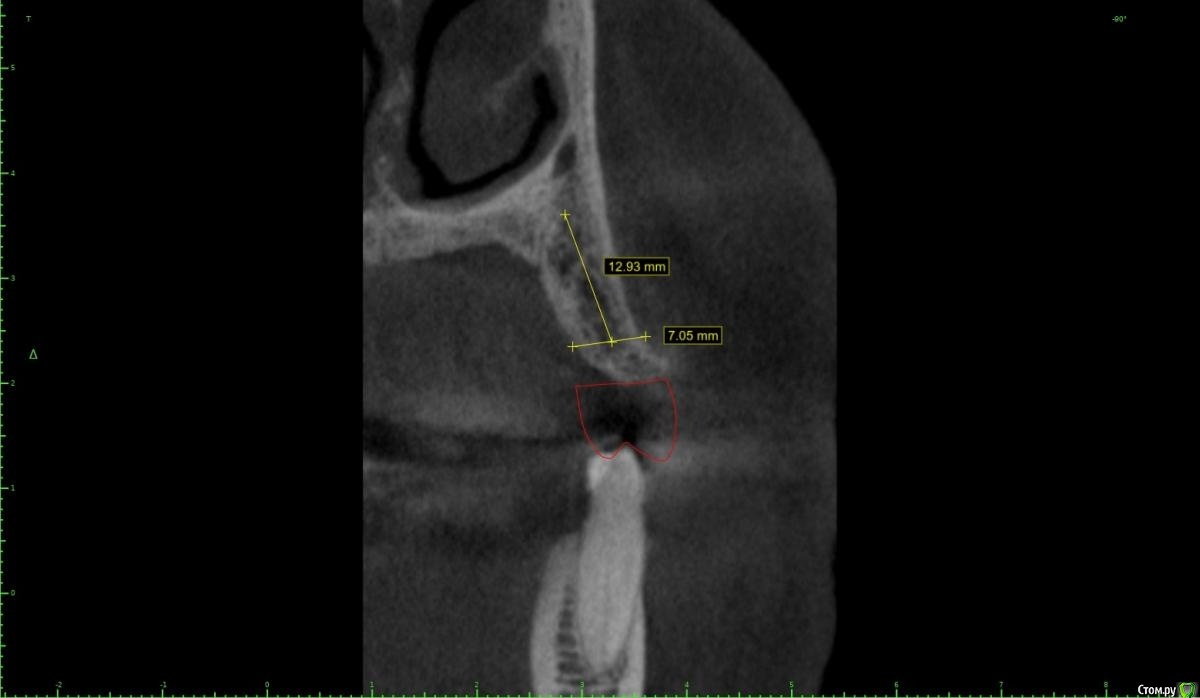

Женька Опубликовано 28 января, 2021 Поделиться Опубликовано 28 января, 2021 Что-то все спрашивают про консоли на имплантатах в области премоляров! Спрошу и я тоже.Коллеги как бы поступили в этом случае?Сам склоняюсь к консоли, но переживаю, что надо бы имплантат пошире, чтобы нагрузку нёс за двоих спокойно. Вариант с двумя винтами не нравится потому как тонковато (не очень) в области 1.4 и необходима редукция около 3мм кости. Ссылка на комментарий

Карен Аванесов Опубликовано 30 января, 2021 Поделиться Опубликовано 30 января, 2021 Что-то все спрашивают про консоли на имплантатах в области премоляров! Спрошу и я тоже.Коллеги как бы поступили в этом случае?Сам склоняюсь к консоли, но переживаю, что надо бы имплантат пошире, чтобы нагрузку нёс за двоих спокойно. Вариант с двумя винтами не нравится потому как тонковато (не очень) в области 1.4 и необходима редукция около 3мм кости.Лично я, в этой ситуации, установил бы 2 имплантата 4х8 с заглублением, в том числе с учетом того что рано или поздно с молярами придется работать. Ссылка на комментарий

Женька Опубликовано 1 февраля, 2021 Автор Поделиться Опубликовано 1 февраля, 2021 ИМХО два винта, но давайте с замерами тогдаДа, наверное вы правы, два по 3.6 проходят Ссылка на комментарий